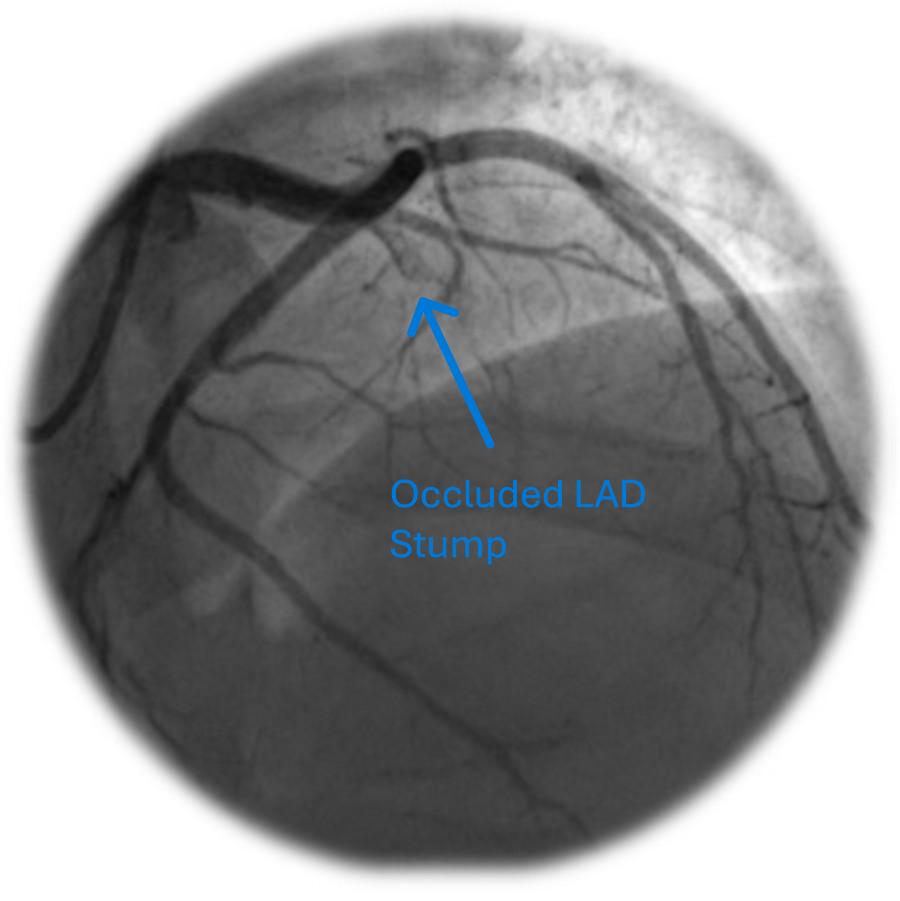

A young man in his early thirties, with a significant medical history of insulin-dependent diabetes mellitus (diagnosed 23 years prior) and ulcerative colitis (diagnosed one year prior), was admitted due to an acute flare-up of ulcerative colitis, characterised by frequent bloody stools and abdominal pain. Despite the initiation of intravenous steroids by the gastroenterology team, he developed symptoms indicative of AMI five days later, confirmed by ST-elevation in the anterior electrocardiogram (ECG) leads (figure 1), and a significant rise in troponin levels, peaking at over 25,000 ng/L. Cardiac echocardiography revealed akinesia of apex, apical inferoseptal and mid-to-apical anteroseptal walls with mildly impaired left ventricular systolic function (figures 2 and 3). Noteworthy was the absence of obstructive atherosclerotic coronary disease in major epicardial vessels, apart from atherothrombotic occlusion in the left anterior descending (figure 4) and diagonal arteries (figure 5), which was addressed with thrombectomy via export catheter, a drug-eluting balloon and intravenous glycoprotein IIb/IIIa inhibitor.